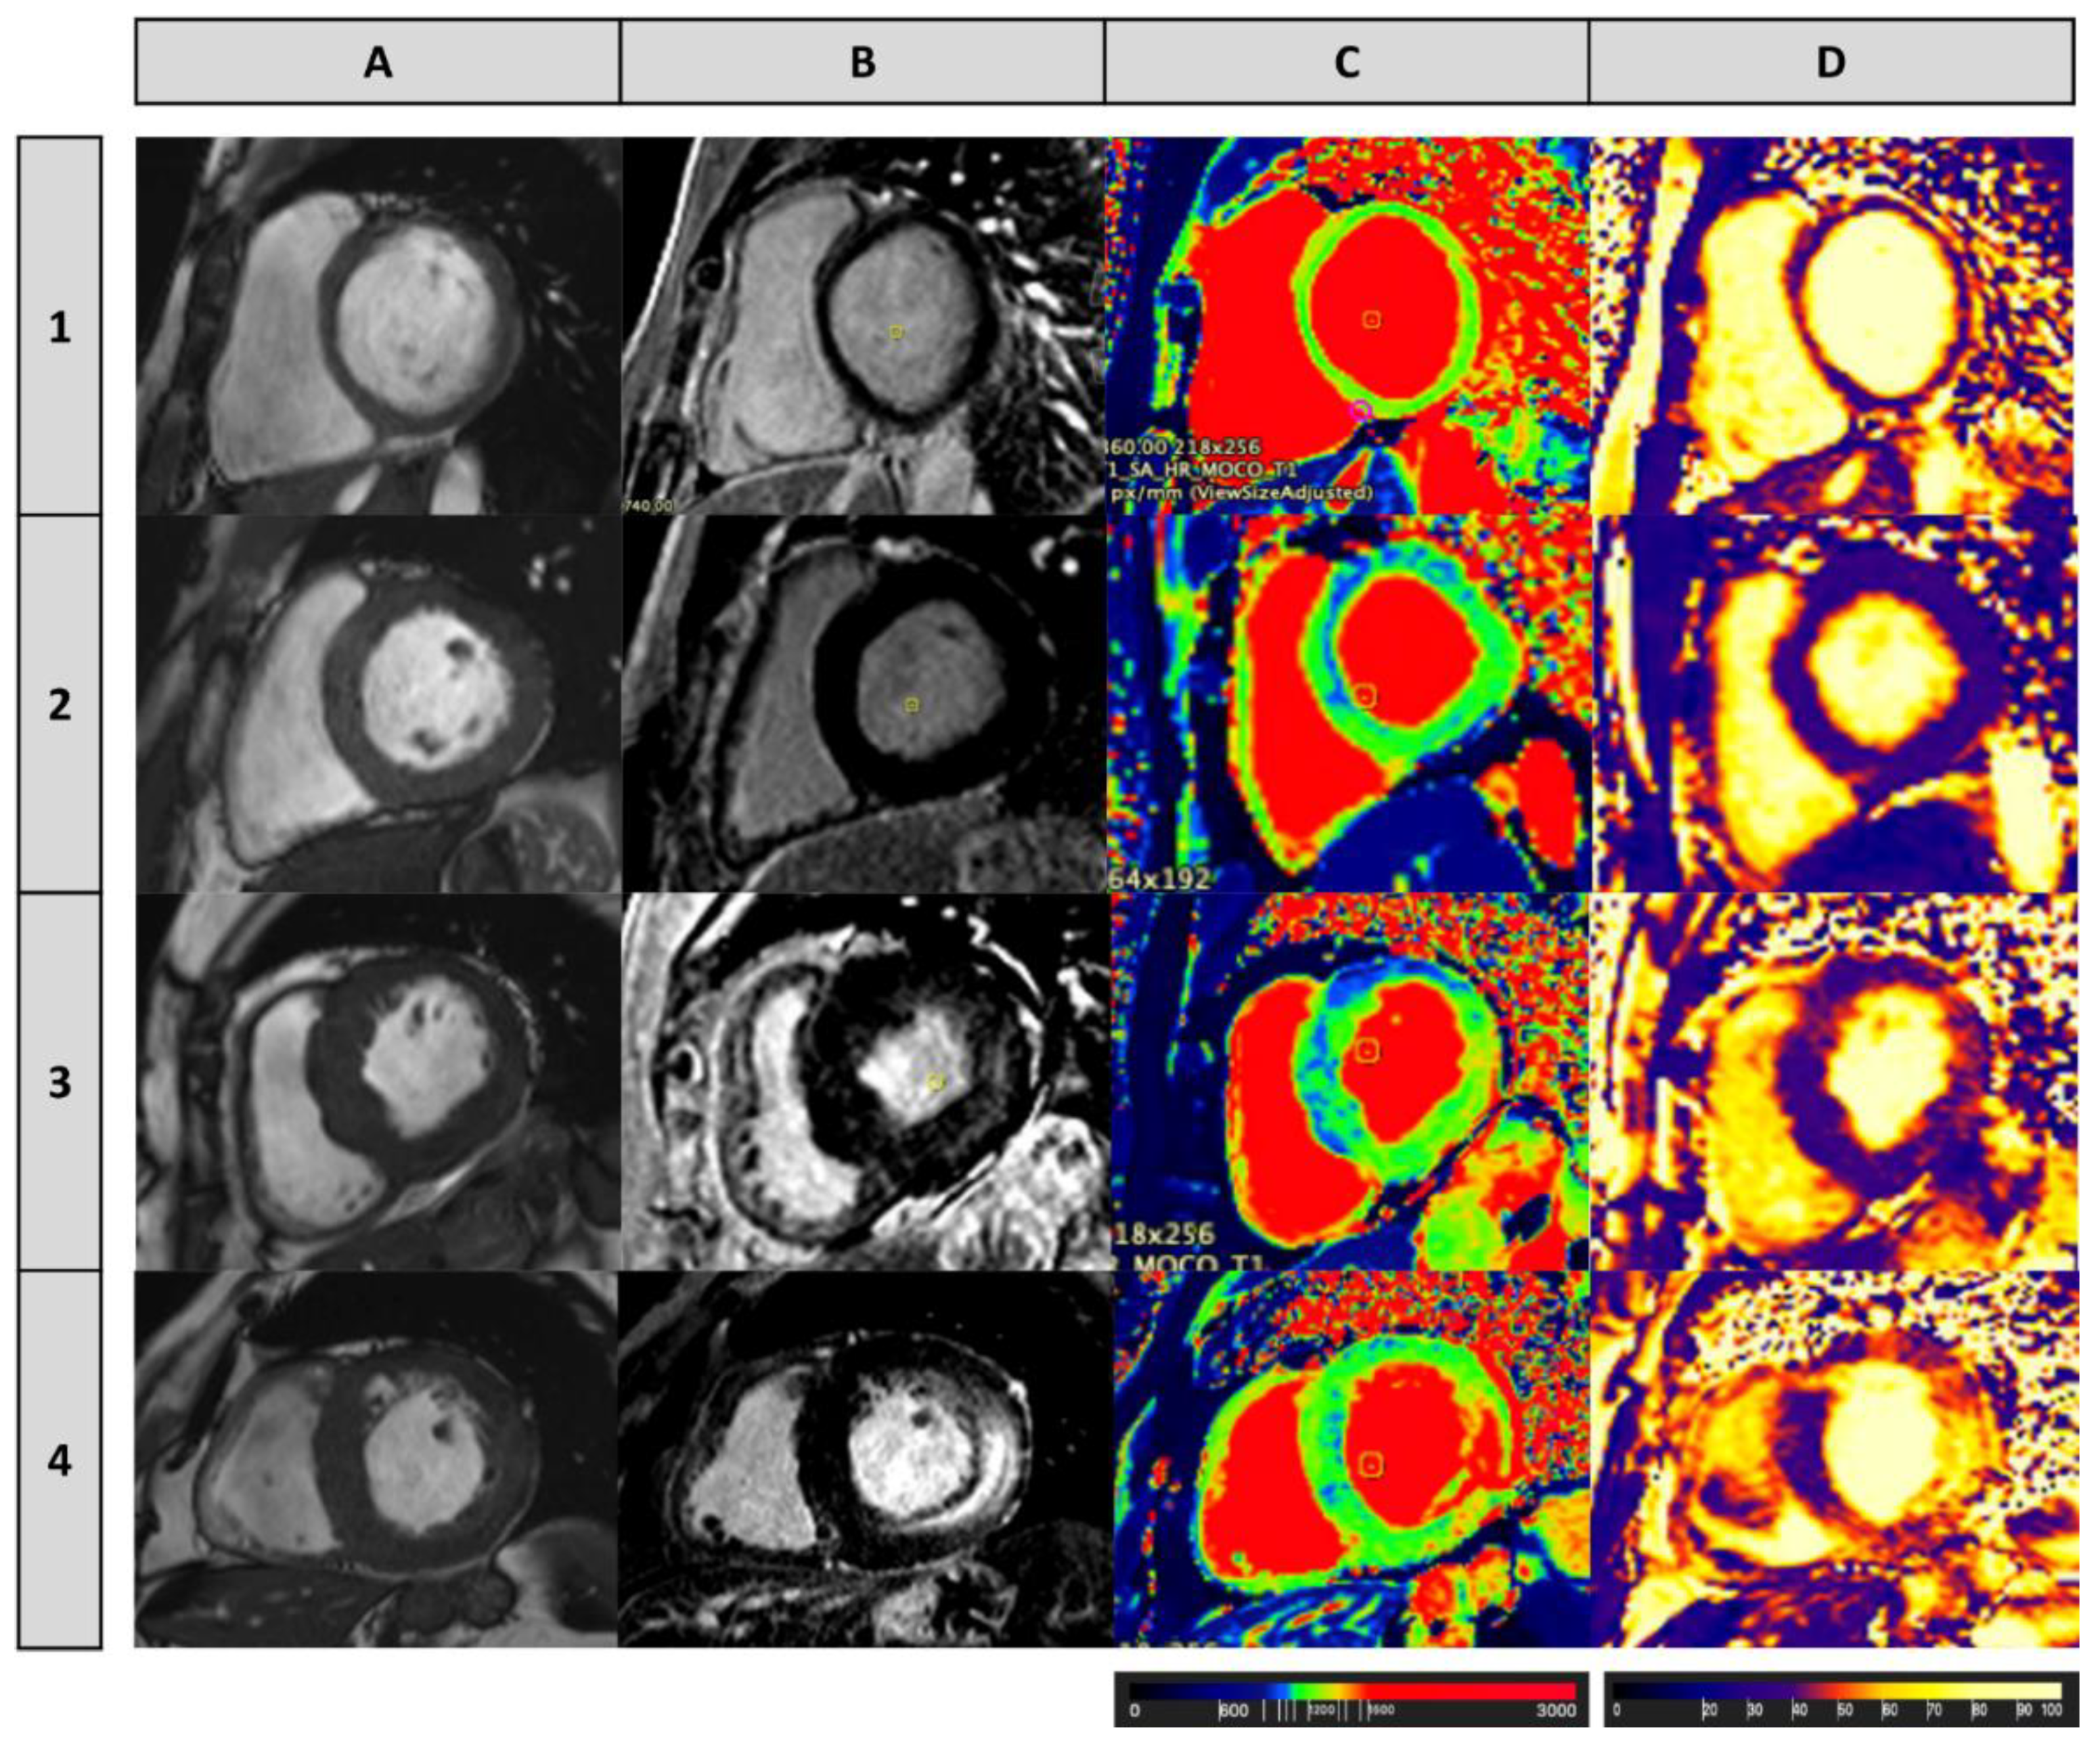

- Sado, D.M.; White, S.K.; Piechnik, S.K.; Banypersad, S.M.; Treibel, T.; Captur, G.; Fontana, M.; Maestrini, V.; Flett, A.S.; Robson, M.D.; et al. Identification and Assessment of Anderson-Fabry Disease by Cardiovascular Magnetic Resonance Noncontrast Myocardial T1 Mapping. Circ. Cardiovasc. Imaging 2013, 6, 392–398. [Google Scholar] [CrossRef] [PubMed] [Green Version]

- Nordin, S.; Kozor, R.; Baig, S.; Abdel-Gadir, A.; Medina-Menacho, K.; Rosmini, S.; Captur, G.; Tchan, M.; Geberhiwot, T.; Murphy, E.; et al. Cardiac Phenotype of Prehypertrophic Fabry Disease. Circ. Cardiovasc. Imaging 2018, 11, e007168. [Google Scholar] [CrossRef] [Green Version]

- Camporeale, A.; Pieroni, M.; Pieruzzi, F.; Lusardi, P.; Pica, S.; Spada, M.; Mignani, R.; Burlina, A.; Bandera, F.; Guazzi, M.; et al. Predictors of Clinical Evolution in Prehypertrophic Fabry Disease. Circ. Cardiovasc. Imaging 2019, 12, e008424. [Google Scholar] [CrossRef]

- Pica, S.; Sado, D.M.; Maestrini, V.; Fontana, M.; White, S.K.; Treibel, T.; Captur, G.; Anderson, S.; Piechnik, S.K.; Robson, M.D.; et al. Reproducibility of native myocardial T1 mapping in the assessment of Fabry disease and its role in early detection of cardiac involvement by cardiovascular magnetic resonance. J. Cardiovasc. Magn. Reson. 2014, 16, 1–9. [Google Scholar] [CrossRef]

- Vijapurapu, R.; Nordin, S.; Baig, S.; Liu, B.; Rosmini, S.; Augusto, J.; Tchan, M.; A Hughes, D.; Geberhiwot, T.; Moon, J.C.; et al. Global longitudinal strain, myocardial storage and hypertrophy in Fabry disease. Heart 2018, 105, 470–476. [Google Scholar] [CrossRef]

- Messroghli, D.R.; Moon, J.C.; Ferreira, V.M.; Grosse-Wortmann, L.; He, T.; Kellman, P.; Mascherbauer, J.; Nezafat, R.; Salerno, M.; Schelbert, E.B.; et al. Clinical recommendations for cardiovascular magnetic resonance mapping of T1, T2, T2* and extracellular volume: A consensus statement by the Society for Cardiovascular Magnetic Resonance (SCMR) endorsed by the European Association for Cardiovascular Imaging (EACVI). J. Cardiovasc. Magn. Reson. 2017, 19, 1–24. [Google Scholar] [CrossRef] [Green Version]

- Pagano, J.J.; Chow, K.; Khan, A.; Michelakis, E.; Paterson, I.; Oudit, G.Y.; Thompson, R.B. Reduced Right Ventricular Native Myocardial T1 in Anderson-Fabry Disease: Comparison to Pulmonary Hypertension and Healthy Controls. PLoS ONE 2016, 11, e0157565. [Google Scholar] [CrossRef] [PubMed] [Green Version]

- Nordin, S.; Kozor, R.; Medina-Menacho, K.; Abdel-Gadir, A.; Baig, S.; Sado, D.M.; Lobascio, I.; Murphy, E.; Lachmann, R.H.; Mehta, A.; et al. Proposed Stages of Myocardial Phenotype Development in Fabry Disease. JACC: Cardiovasc. Imaging 2019, 12, 1673–1683. [Google Scholar] [CrossRef]